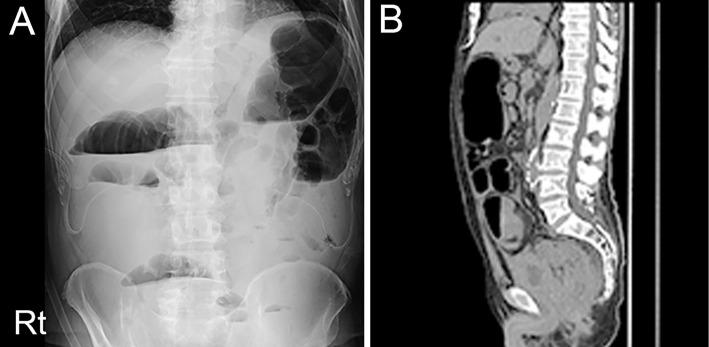

We herein report a 70-year-old man with recurrent multiple cerebral infarctions under warfarin therapy who was finally diagnosed with Trousseau's syndrome resulting from advanced bladder cancer. A histological examination of the mesenteric lymph nodes revealed metastasis of micropapillary urothelial cancer with positive mucin markers CA125 and MUC1. Blood examinations also indicated elevated tumor markers, such as CA19-9 and CA125. To our knowledge, this is the first report of Trousseau's syndrome in a patient with bladder micropapillary urothelial cancer in which mucin involvement was clearly proven by histological and serological examinations.

我们在此报告一例 70 岁男性患者,在华法林治疗下反复发作多发性脑梗死,最终诊断为晚期膀胱癌所致的 Trousseau 综合征。肠系膜淋巴结的组织学检查显示微乳头状尿路上皮癌转移,黏蛋白标志物 CA125 和 MUC1 阳性。血液检查也提示肿瘤标志物如 CA19-9 和 CA125 升高。据我们所知,这是首例组织学和血清学检查明确证实有黏蛋白参与的膀胱癌微乳头状尿路上皮癌患者发生 Trousseau 综合征的病例报告。